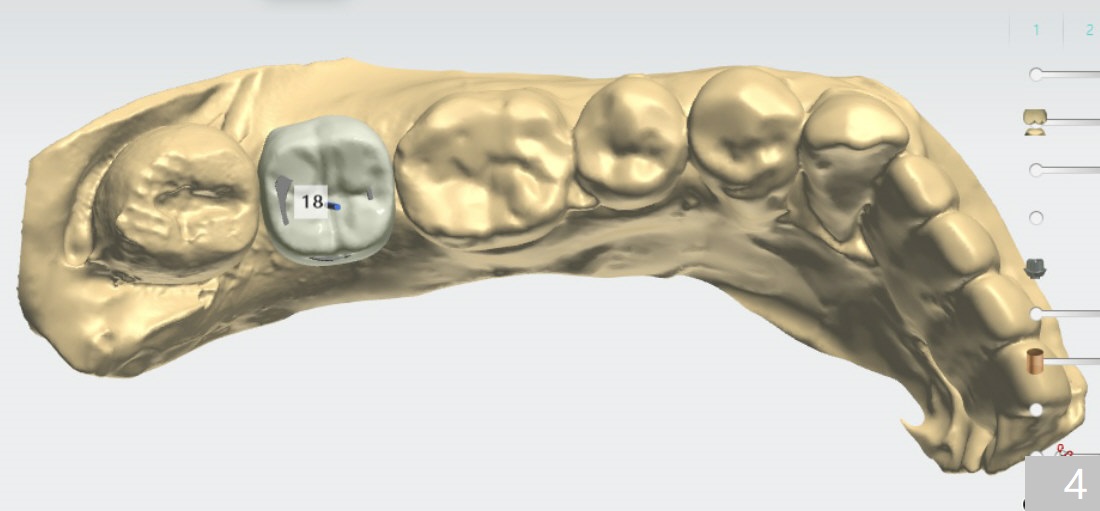

植体周围骨缺损

完成钻洞后,检查近中颊侧缺损,必要时植骨,收集钻头上的骨粉